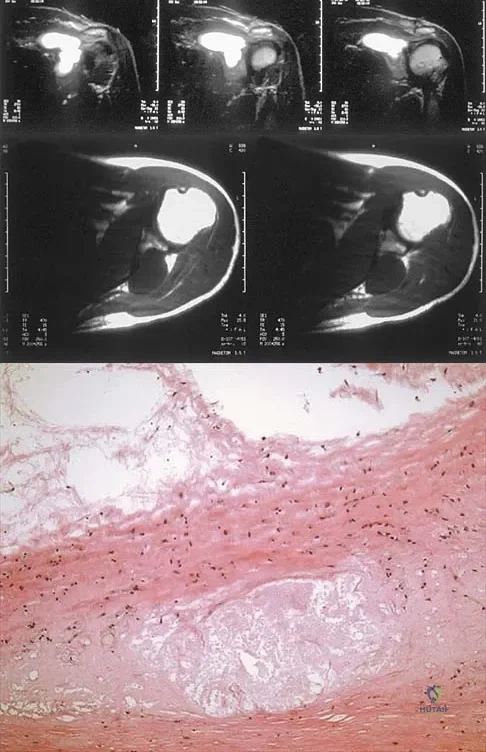

A 37-year-old man has left shoulder pain and weakness. Coronal T1- and axial T2-weighted MRI scans are shown in Figures 17a and 17b. The biopsy specimen is shown in Figure 17c. What is the most likely diagnosis?

Explanation